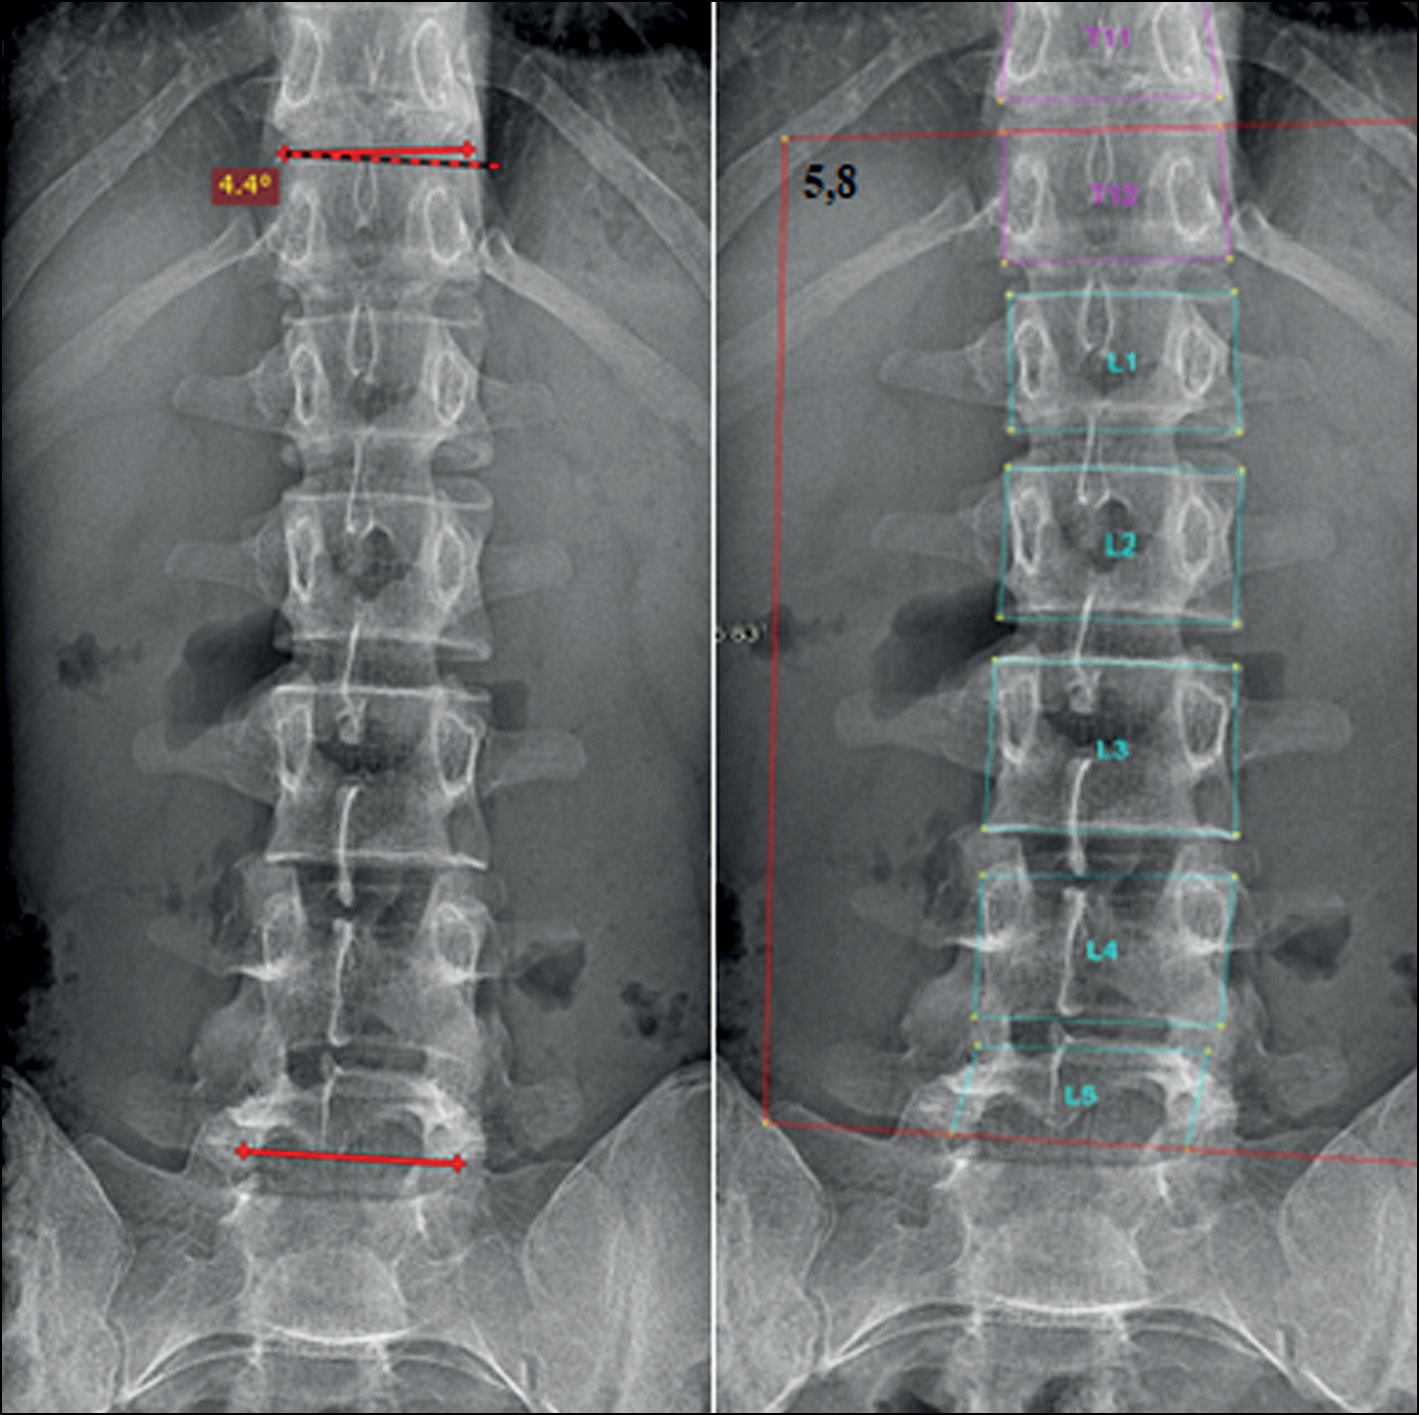

The bulk of this work was performed in a hospital where adolescents are screened for scoliosis, as part of multiple examinations for medical commissions, to determine whether adolescents match the criteria for army enlistment. Thus, radiographs in test set 1 and test set 2 were divided according to the severity classification included in Federal Law No. 565, where any small curves with angles <10° are considered grade 1 scoliosis [16]. The new automatic system for evaluating scoliosis on digital radiographs can help radiologists to define the scoliosis grade and measure the curve’s angle, particularly in situations such as screening for scoliosis and at times of heavy workload in outpatient clinics. In these situations, radiologists can use the program as an objective tool, increasing the accuracy of scoliosis evaluation on frontal radiographs because the interobserver variability can be avoided if radiologists use the same instrument. Moreover, it can significantly save the radiologist’s time. In addition, Cobb’s angles measured by the system were acceptable, with no significant clinical variability in most of the evaluated curves. Fig. 4 shows an example of how the system works.

Fig. 4. X-ray image showing grade 2 scoliosis. Analysis by the system (left) and by the radiologist (right). The radiologist did not measure the thoracolumbar curve as the lower EV is not shown in the image.